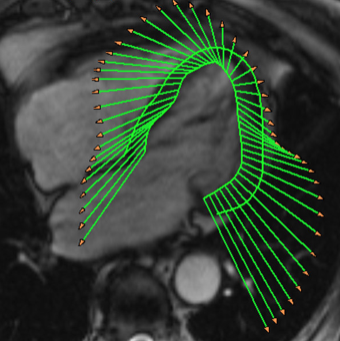

- Strainanalyse